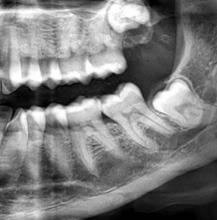

Root Canal Treatments

Crowns, Bridges, and Dentures